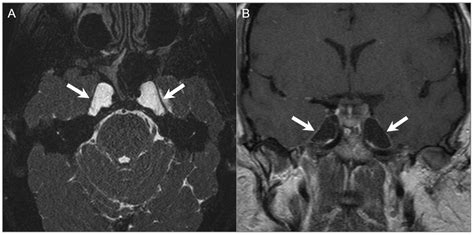

To confirm the presence of a tumor, specialists typically employ a variety of advanced imaging techniques. A standard physical examination is often followed by specialized diagnostic tests to map the extent of the tumor:

MRI (Magnetic Resonance Imaging) Provides high-resolution images of soft tissues, nerves, and the brain.